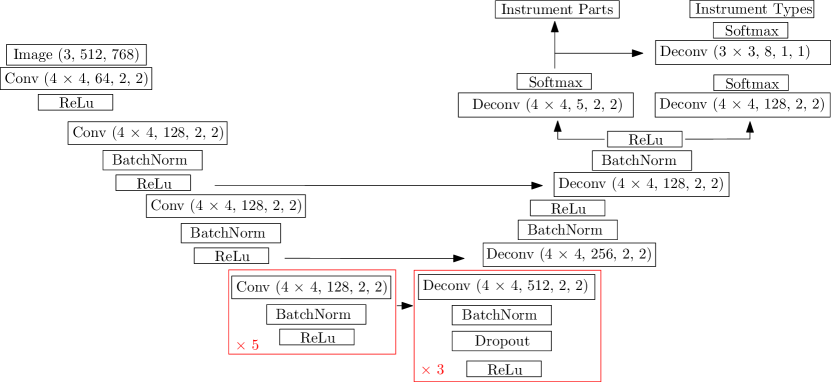

III-A National Center for Tumor Diseases (Dresden)

Method 1 was from a team at the National Center for Tumor Diseases (NCT) in Dresden. It consisted of Sebastian Bodenstedt, Isabel Funke and Stefanie Speidel. Their method was based on residual CNNs and the topology of the network can be seen in Fig. 5. Before training, they cropped the black borders off the images, equally removing rows and columns to leave an image of resolution and then downsampled the image to . Random augmentations of increasing the pixel value by , vertical and horizontal flips, zooms of and rotations of degrees. Training was performed for 200 epochs using a categorical cross entropy as a loss function and Adam as the optimizer.